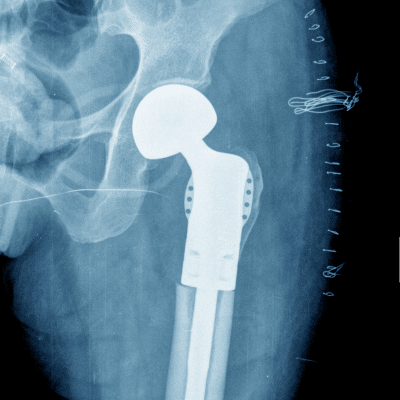

Prótesis de cadera o rodilla

Cirugía protésica de rodilla y cadera